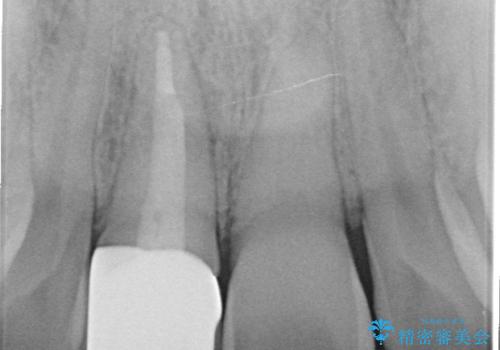

- 右上1番目の前歯の変色が気になるといらっしゃった方の症例です。

再根管治療後、オールセラミッククラウンによる補綴を行いました。

- オールセラミッククラウン…¥100,000、仮歯…¥10,000、ファイバーコア…¥20,000、精密根管治療費別途費用は治療当時の料金となります